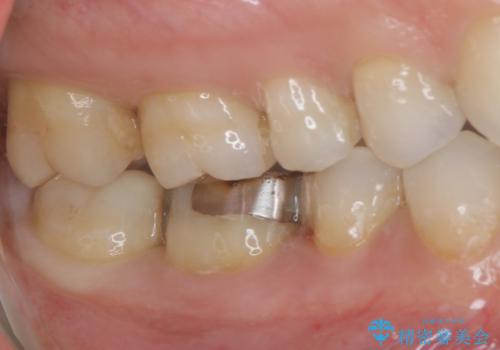

- 歯と歯の間によくものが詰まるということで来院された患者様です。

銀歯のある部分によくものが詰まるようで、診断の結果セラミックにて治療を行う計画を立てて

銀歯を外し他の歯も虫歯があったためそちらも一緒に治療を行いました。